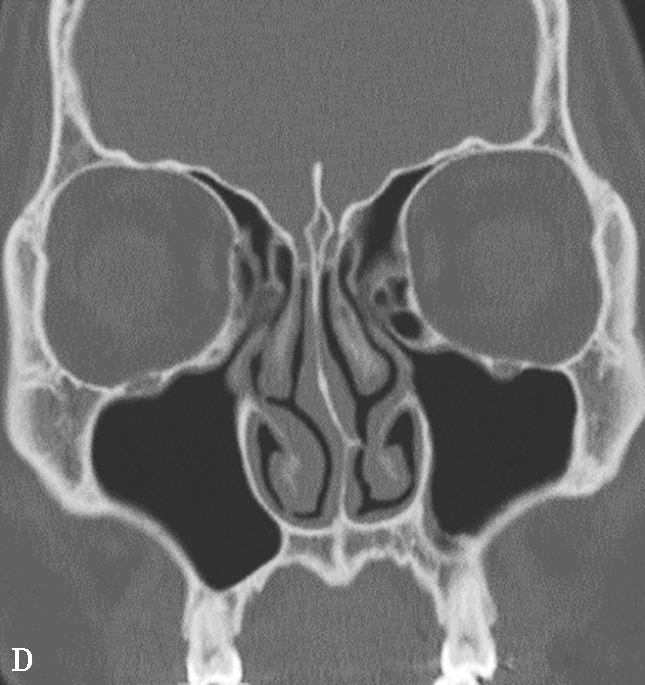

图1-3-1 鼻丘气房及额气房CT解剖

A~C.鼻丘气房(五角星),额气房(星),钩突(白箭),筛骨纸板(箭头)

鼻窦过度气化、未发育或发育不良均以额窦最为常见,过度气化的额窦可伸展至颧突,向上至额结节水平以上,或超过眶顶至视神经孔(图1-3-9A),未发育或发育不良的额窦表现为额窦间隔缺如,只有单侧一个额窦窦腔,或双侧额窦窦腔均发育不良(图1-3-9B)。眶上筛房是额窦区域外侧的气房,亚洲人少见,冠状面上表现为随着扫描层面的后移,它的横径逐渐延长(图1-3-9C)。鼻中隔偏曲是指鼻中隔向一侧或两侧弯曲(图1-3-9D),或鼻中隔一侧或两侧局限性凸起,可引起鼻塞、鼻出血以及头痛。鸡冠可以发生气化,引流至额隐窝,如果开口闭塞,鸡冠内可产生黏膜囊肿(图1-3-9E)。

图1-3-9 其他常见解剖变异

A.额窦过度气化;B.额窦未发育;C.眶上筛房;D.鼻中隔偏曲,形成嵴;E.鸡冠气化并感染